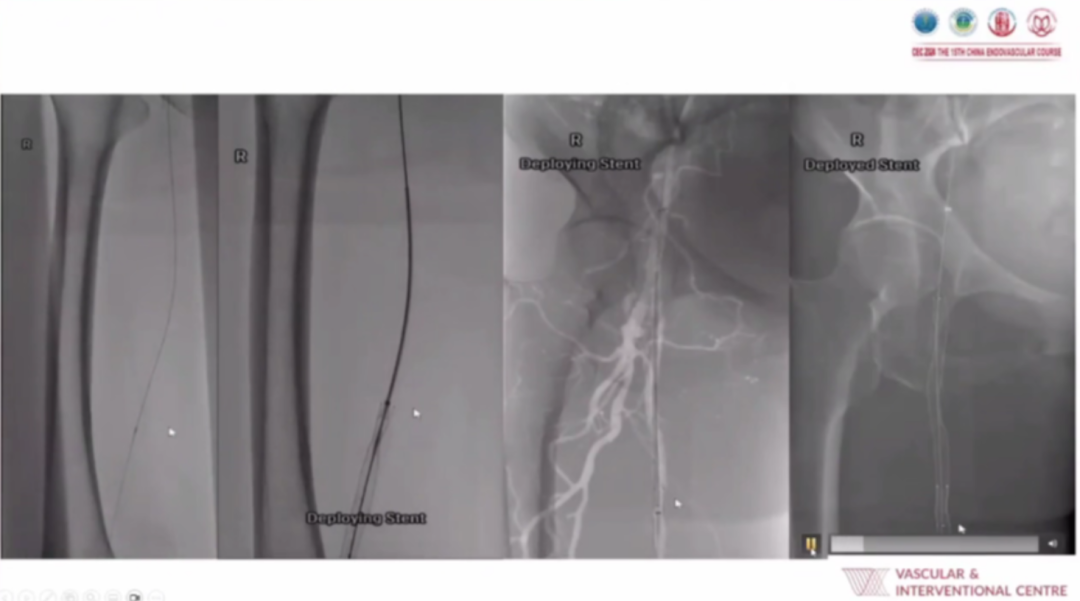

手术实施时,麻醉方式以静脉镇静或局部麻醉为主(仅大范围伤口清创时选用全麻);入路策略优先选择桡动脉处理髂动脉、股浅动脉(SFA)病变,顺行入路为首选;技术上借助CO₂造影、SMART Perfusion技术实时评估血流,配合积极的抗血小板治疗,还会灵活运用Auryon激光斑块切除术、改良深静脉动脉化等手段应对复杂病变。

从典型病例影像(包括常规CLTI病例、需激光斑块切除联合支架植入的病例、改良深静脉动脉化病例等)可见,术后通过血管造影、血流灌注成像等能清晰看到病变血管的血流恢复情况,验证了日间手术策略在CLTI肢体挽救中的有效性。